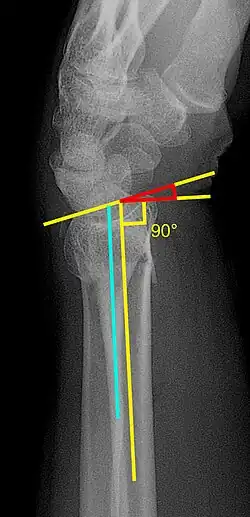

X-ray of the affected wrist is required if a fracture is suspected. Posteroanterior, lateral, and oblique views can be used together to describe the fracture.[5] X-ray of the uninjured wrist should also be taken to determine if any normal anatomic variations exist before surgery.[5]

Various kinds of information can be obtained from X-rays of the wrist:[5]

Lateral view

- Carpal malalignment - A line is drawn along the long axis of the capitate bone and another line is drawn along the long axis of the radius. If the carpal bones are aligned, both lines will intersect within the carpal bones. If the carpal bones are not aligned, both lines will intersect outside the carpal bones. Carpal malignment is frequently associated with dorsal or volar tilt of the radius and will have poor grip strength and poor forearm rotation.[5]

- Tear drop angle - It is the angle between the line that pass through the central axis of the volar rim of the lunate facet of the radius and the line that pass through the long axis of the radius. Tear drop angle less than 45 degrees indicates displacement of lunate facet.[5]

- Antero-posterior distance (AP distance) - Seen on lateral X-ray, it is the distance between the dorsal and volar rim of the lunate facet of the radius. The usual distance is 19 mm.[5] Increased AP distance indicates the lunate facet fracture.[8]

- Volar or dorsal tilt - A line is drawn joining the most distal ends of the volar and dorsal side of the radius. Another line perpendicular to the longitudinal axis of the radius is drawn. The angle between the two lines is the angle of volar or dorsal tilt of the wrist. Measurement of volar or dorsal tilt should be made in true lateral view of the wrist because pronation of the forearm reduces the volar tilt and supination increases it. When dorsal tilt is more than 11 degrees, it is associated with loss of grip strength and loss of wrist flexion.[5]

Posteroanterior view

- Radial inclination - It is the angle between a line drawn from the radial styloid to the medial end of the articular surface of the radius and a line drawn perpendicular to the long axis of the radius. Loss of radial inclination is associated with loss of grip strength.[5]

- Radial length - It is the vertical distance in millimetres between a line tangential to the articular surface of the ulna and a tangential line drawn at the most distal point of radius (radial styloid). Shortening of radial length more than 4mm is associated with wrist pain.[5]

- Ulnar variance - It is the vertical distance between a horizontal line parallel to the articular surface of the radius and another horizontal line drawn parallel to the articular surface of the ulnar head. Positive ulnar variance (ulna appears longer than radius) disturbs the integrity of triangular fibrocartilage complex and is associated with loss of grip strength and wrist pain.[5]